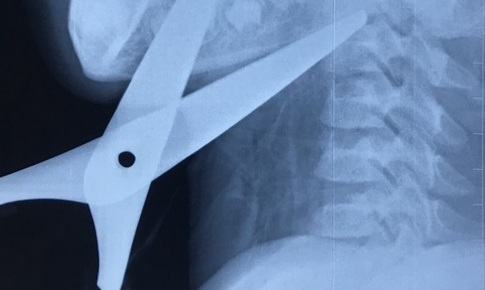

kéo đâm xuyên cổ

Cứu sống bé trai bị kéo đâm xuyên cổ

SKĐS - Mới đây, bé trai 7 tuổi ở Ninh Bình nhặt được cây kéo của bạn về để cắt giấy làm diều. Trong lúc chạy chơi, bé chẳng may bị ngã vào chiếc kéo đó. Cú va chạm khiến cháu bị kéo đâm xuyên cổ.